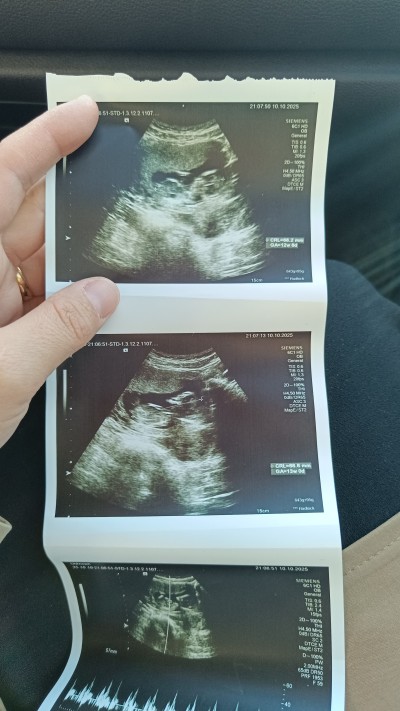

Doktor gordum ama soylemivem dedi tahminim var tam goremiyorum dedi o yuzden soylemedi

Gebelik haftası 11+6

Bebek kendini göstermiyor olabilir zaten zor şimdi hani doktor görse bile yüzde 50 tahmini olarak şimdi erken 14 haftanizda giderseniz daha net olur hanımlar o erkeği nasıl gördü şaşırdım

Bazen goruyorum keseye gore tahminler yapiyorlar

Tewekkur ederim hepimizinsadece keseye gore tahmin dogrumu oluyor bilmiyorum

Cunki mayalanma suresi gec olunca oyle oluyor bendede 13.2olmali ama 11+6hafta ultrason

Ben ultrason kâğıdın bakarak konuştum . Ölçüme göre değil tabi sadece tahmin bu çünkü bu ultrason kağıdında nub tam görülmüyor bacaklar kapali

Erkek bence canm ordan bişey çıkmış çünkü 😊

Kesinlikle kız bebek bu iki çizgi var öğrenince yaz bak kesinlikle kız

Nub kısmına bak anlarsın